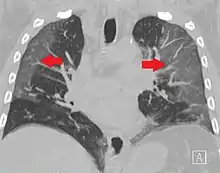

CT image showing diffuse GGOs throughout both lungs. An abscess is also noted in the right lung (screen left). - Adenocarcinoma in situ of the lung